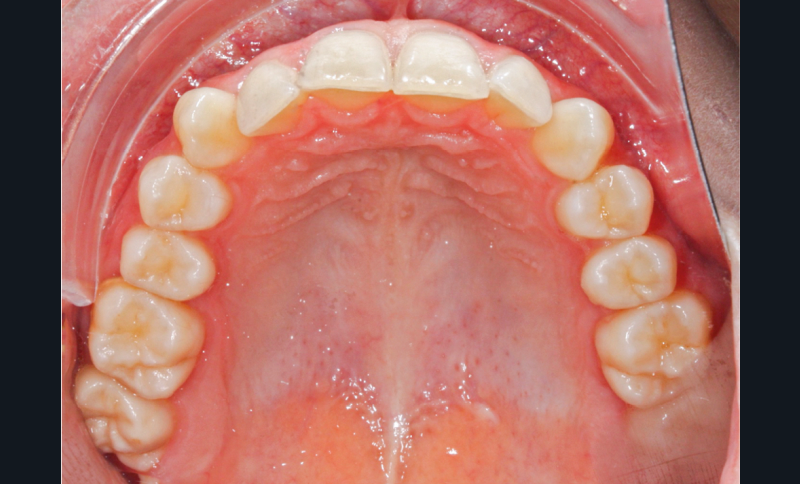

L’examen intra-arcade met en évidence une hygiène bucco-dentaire irréprochable, favorable à un traitement en technique linguale. Le phénotype parodontal est fin dans la région incisivo-canine mandibulaire. L’encombrement est estimé à 8 mm à la mandibule et à 4 mm au maxillaire (fig. 1). Les arcades ont des formes similaires, en U. Les rapports inter-arcades mettent en évidence une classe 1 d’Angle molaire, une classe 2 d’Angle canine et une supraclusion antérieure (recouvrement : 5 mm ; surplomb diminué). Les milieux inter-incisifs sont déviés entre eux avec une origine mixte (= 1,5 mm) (fig. 2).